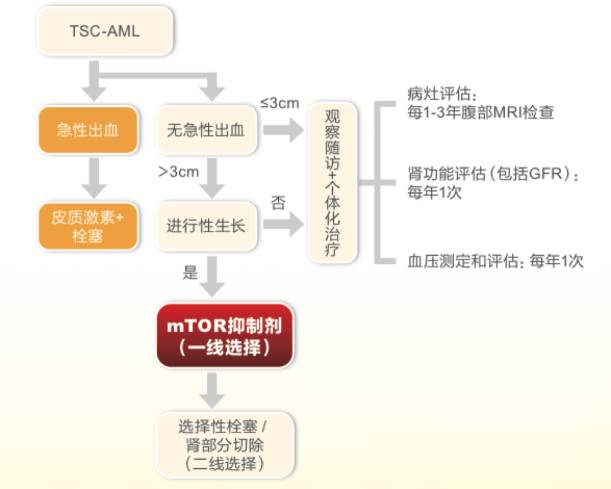

在没有研发出针对性药物之前,如果面对破裂出血,临床上主要采用栓塞止血,特别严重的情况,选择手术,以外科干预为主。但近些年因为有了依维莫司这样的mTOR抑制剂的出现,可抑制细胞生长与增殖,抑制血管生成,改善TSC相关的全身症状,临床医生都是首选药物治疗,只有面对紧急情况,才考虑手术,而医生一般不会主动选择手术。

国外医生一般建议患者长期服药,因为一旦停药,几个月疾病会反复。今年5月份,中国首部《结节硬化症肾血管平滑肌脂肪瘤诊治的专家共识》发布,指南借鉴了国外多个版本指南推荐,并结合中国的发病特点,制定了适合中国临床医生操作的规范化的诊疗流程,通过推广和普及,提高国内TSC诊疗水平。